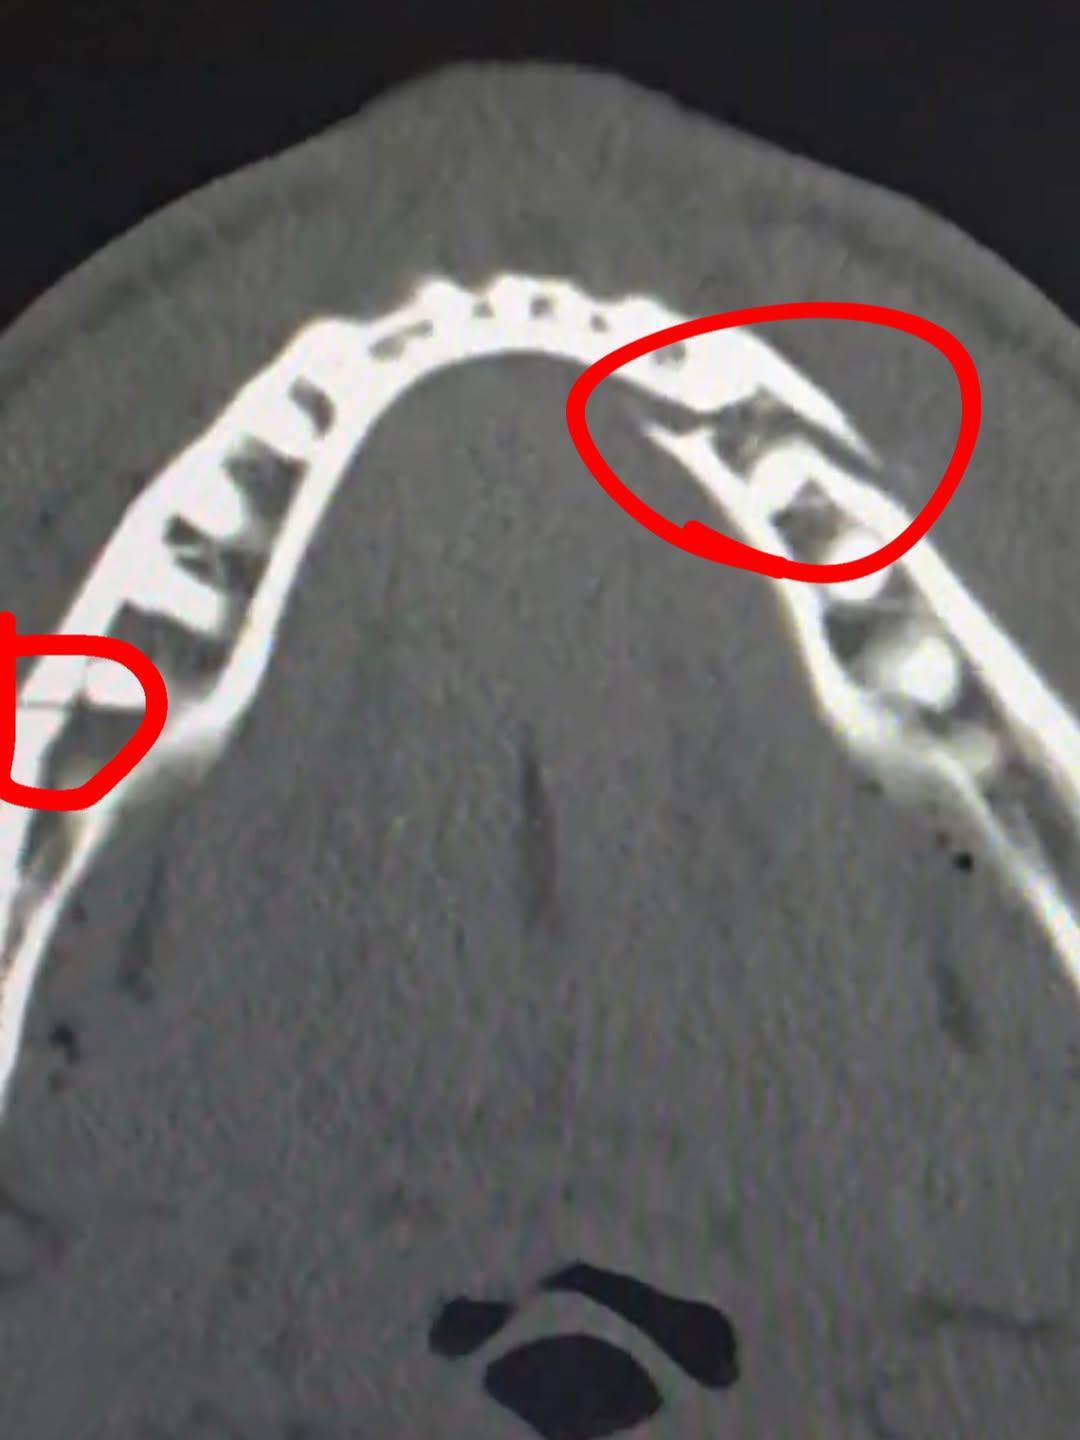

Позднее он выложил рентгеновский снимок травмы. «Двойной перелом челюсти. Дайте мне Канело (Сауля Альвареса. — РБК) через десять дней», — подписал свой пост Пол. Также он выложил ролик с больничной койки.